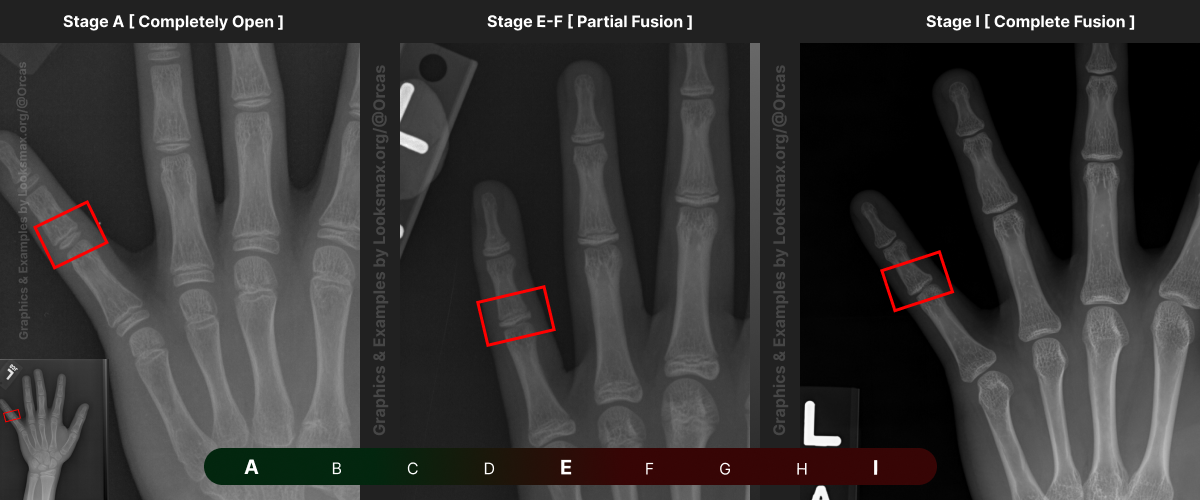

Bonetype: 1st Metacarpal (thumb)

Check & use the chart below to figure out where you are. Then write your result on a piece of paper or a text file.

Bonetype: 1st Proximal Phalanx

Bonetype: 3rd Proximal Phalanx